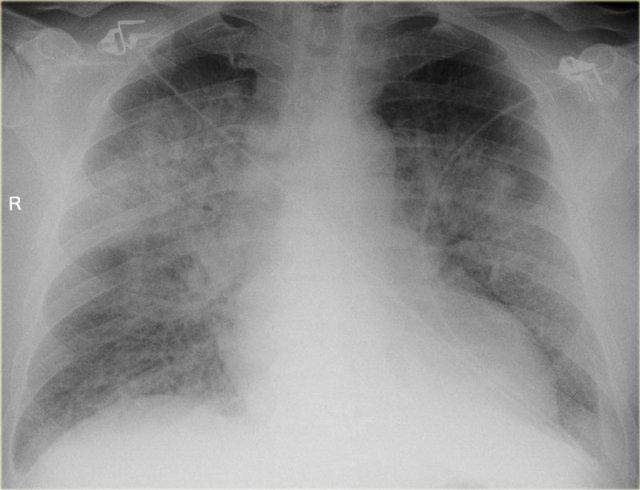

Đông đặc lan tỏa

Nguyên nhân phổ biến nhất của đông đặc lan tỏa là phù phổi do suy tim.

Đây còn được gọi là phù phổi do tim, để phân biệt với các nguyên nhân khác nhau của phù phổi không do tim.

Kích thước tim tăng thường là yếu tố phân biệt giữa phù phổi do tim và không do tim.

Cần tìm kiếm các dấu hiệu khác của suy tim như tái phân bố lưu lượng máu phổi, đường Kerley B và tràn dịch màng phổi.